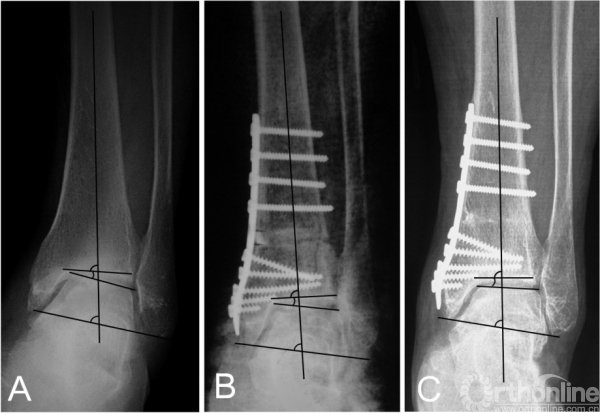

对于内翻型踝关节OA,选择合适的截骨矫形术式可以改善愈后。常用的术式大体分为三类:外侧闭合楔形截骨、内侧开放楔形截骨和关节内(Plafond)截骨术。尽管Stamatis等指出,不同术式的选择并不影响临床及影响学结果,或骨愈合时间。然而,虽然闭合截骨的手术操作相对容易,如果患者条件允许,我们更倾向于内侧开放楔形截骨术(图2)。

图2 患者为52岁女性,术前X线提示为Takakura-3A期踝关节骨关节炎(2A);行踝上截骨合并腓骨截骨,术后关节面匹配度及负重力线均得到矫正(2B);术后12个月及47个月的随访提示矫形效果得到维持,改良Takakura分期降至1期。

图3 术前X线片提示内翻型踝关节骨关节炎(3B期),行踝上截骨合并腓骨截骨术后2年,患者的关节匹配度及负重力线均矫正良好,距骨倾斜角从术前的14.5°降至1.2°

在踝上截骨时,是否及何时需要辅助腓骨截骨目前尚无定论。在早期的报道中,腓骨截骨被要求作为常规术式来矫正踝关节内翻畸形;然而,后来的一些研究则要求在所有患者中保留腓骨。而我们只在需要时才辅助腓骨截骨,评估内容分为术前和术中。术前评估包括:1)患侧TC角较健侧减小超过5°或存在内翻改变;2)存在腓骨骨折畸形愈合;3)患者因胫骨骨骺损伤史而导致腓骨相对较长。术中主要评估在胫骨远端关节面积距骨复位时,是否存在外侧阻挡。生物力学研究指出,在胫骨远端关节面外翻时,胫距关节的接触压强并未随之显著外移,而是在内侧形成峰值压强;只有在腓骨截骨后,胫距关节的接触压强才随着外翻角度的增大逐渐转向外侧。因此,在这种情况下,腓骨截骨可以促进关节协调性的恢复,以及接触压力的外移。根据我们的研究结果,腓骨截骨组的患者,TT角的改善程度更加显著(图3)。

我们认为,在非终末期内翻型踝关节OA患者,通过踝上截骨来矫正负重力线及改善关节适配性是值得的,即使对于TT较大的患者。因为踝上截骨可以关节接触压强得到重新分布,外移踝关节机械轴,延缓甚至逆转OA的进程;甚至通过术后负重改变,使TT重新恢复至正常范围(图5)。我们认为,影像学的改变有时是需要时间的,正如OA的形成原因。Cheng等报道,所有患者在随访时内侧间隙逐渐增宽,且常需要1年以上时间才能使踝关节间隙改善至理想程度。

图5 术前的距骨倾斜角(TT)为10.7°(5A),术后矫正至7.8°(5B);然而术后32个月随访时TT则已经恢复至1.5°(5C)